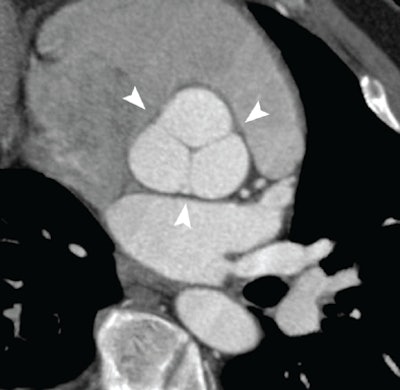

| Normal aortic root at coronary CTA illustrating the complex cornet shape above the basal ring. Image courtesy of Dr. Geoffrey Rubin. |